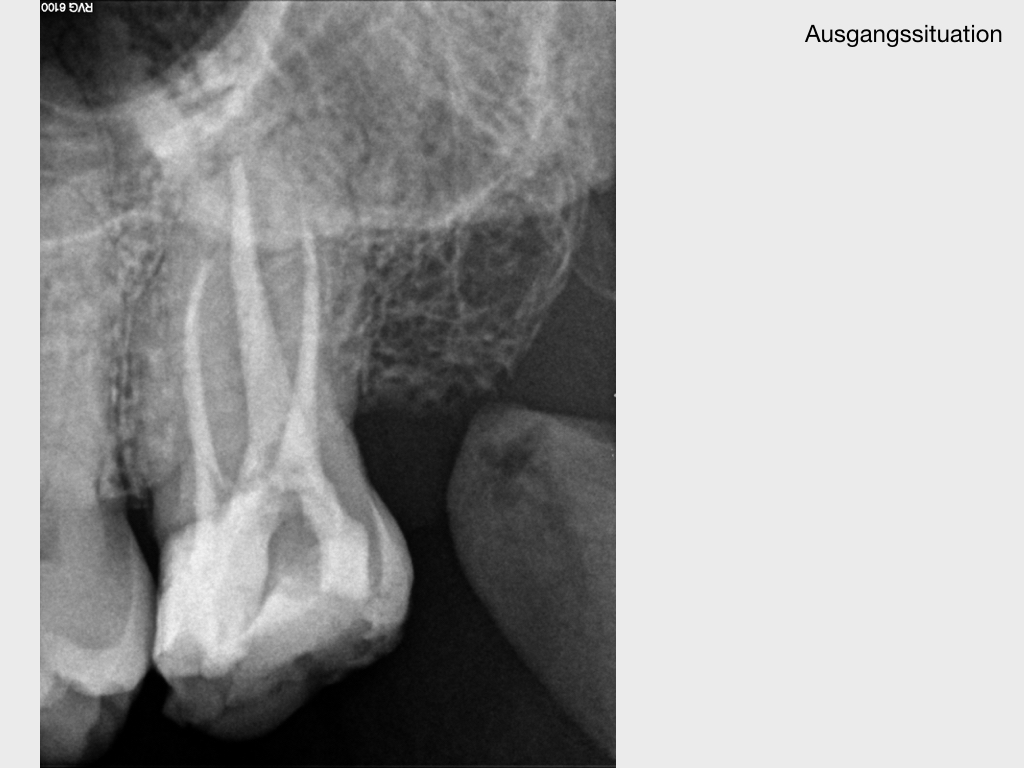

WSPick1.001

Pick, Pick (1)